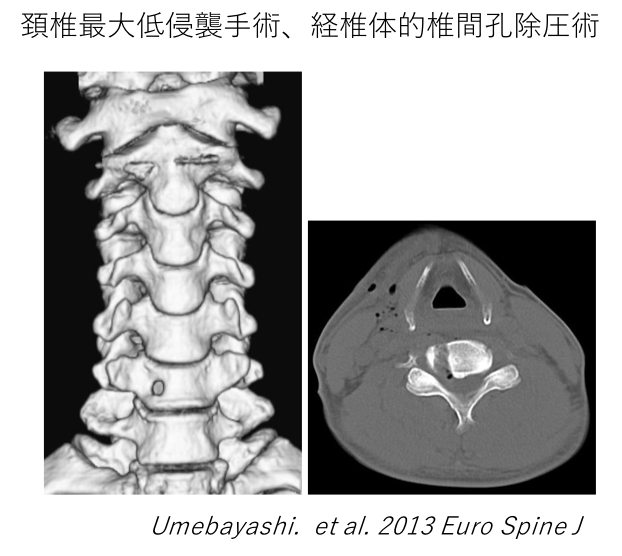

また、前方からは一般的に行われている前方固定術だけでなく、骨に6mmの鍵穴のみをあけて行う経椎体的椎間孔除圧術を行っています。適応できる病態は限られますが、前方固定術による無駄な固定による可動性の消失と、隣接椎間の障害(隣の骨に負担をかけることによる再発)を回避します。また、多椎間に及ぶ場合は前方固定術と経椎体的椎間孔除圧術を併用することで手術範囲とともに固定範囲を少なくすることができます。

頸椎最大低侵襲手術、経椎体的椎間孔除圧術